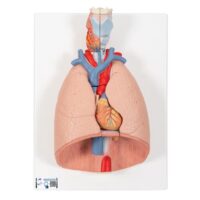

UK 3B Lung Model with Larynx

This full lung model with larynx is first class. The high quality lung model contains the following removable parts for added anatomical detail

UK 3B Full Lung Model with larynx The lung model with larynx is first class. The high quality lung model contains the following removable parts for added anatomical detail:

- 2-part larynx

- Trachea with bronchial tree

- 2-part heart

- Subclavian artery and vein

- Vena cava

- Aorta

- Pulmonary artery

- Esophagus

- 2-part lung (front halves removable)

- Diaphragm